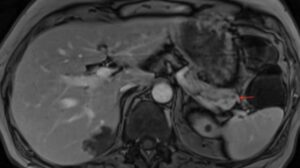

Ο εργαστηριακός έλεγχος ανέδειξε σημαντικά αυξημένα επίπεδα αγγειοδραστικού εντερικού πεπτιδίου (VIP), ενώ η απεικόνιση κατέδειξε όγκο στην ουρά του παγκρέατος με ηπατικές μεταστάσεις στα τμήματα VI, VII και III. Από το ατομικό αναμνηστικό αναφερόταν λαπαροσκοπική χολοκυστεκτομή.